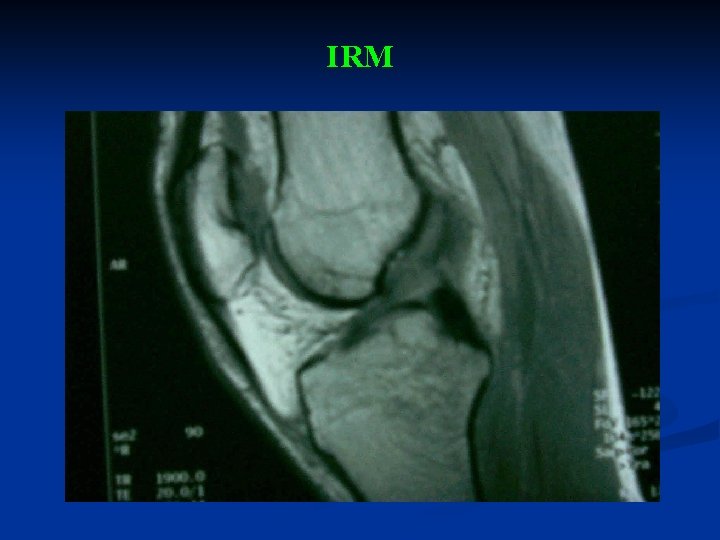

III. EXAMENS COMPLEMENTAIRES n RADIOGRAPHIES DU GENOU F+P: n n ECHOGRAPHIE: n n Recherche de fracture, d’arrachement osseux, d’épanchement. Epanchement. IRM: n Préciser les différentes lésions.

IRM